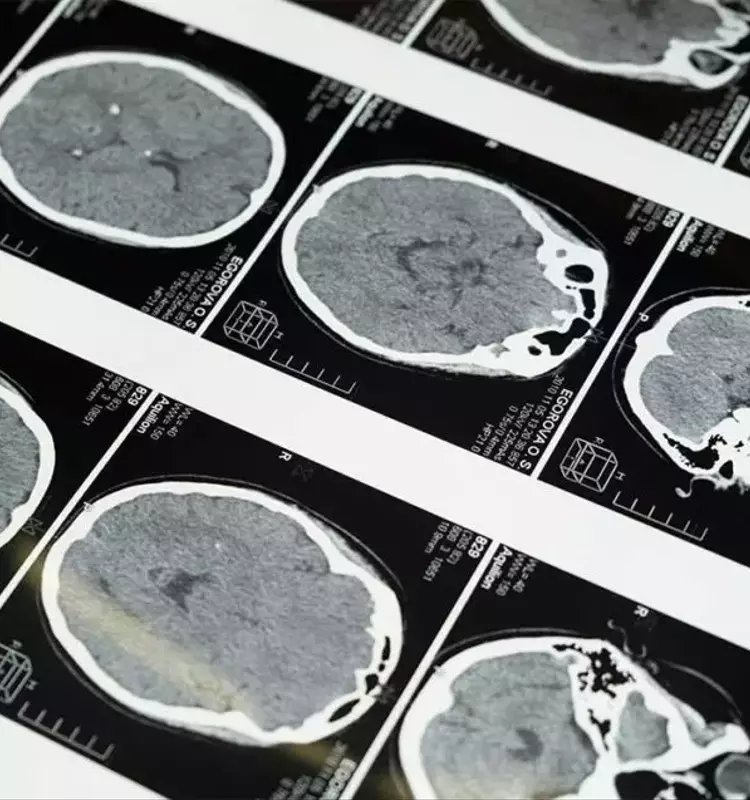

La investigación involucró a casi 800 participantes sin demencia, con una edad promedio de 39 años. Se evaluaron sus niveles de vitamina D en la sangre al inicio del estudio y, aproximadamente 16 años después, se realizaron escáneres cerebrales para cuantificar las proteínas tau y beta amiloide, ambas vinculadas al Alzheimer. Se clasificaron los niveles de vitamina D como altos si superaban los 30 ng/mL y bajos si estaban por debajo de esta cifra; un tercio de los participantes presentaba deficiencia. Los investigadores ajustaron los datos por factores como la edad, el género y la presencia de síntomas depresivos, que también podrían influir en los niveles de tau.

Los resultados indicaron claramente que concentraciones más elevadas de vitamina D se correlacionaban con niveles más bajos de proteína tau, pero no se encontró una relación similar con la proteína beta amiloide. Estos hallazgos son alentadores, ya que la mediana edad es un momento propicio para intervenir en factores de riesgo y potencialmente modificar la trayectoria del desarrollo del Alzheimer. Aunque el estudio no establece una relación de causa y efecto, sí sugiere una vía prometedora para futuras investigaciones sobre el uso de la vitamina D en estrategias preventivas y terapéuticas contra el Alzheimer.